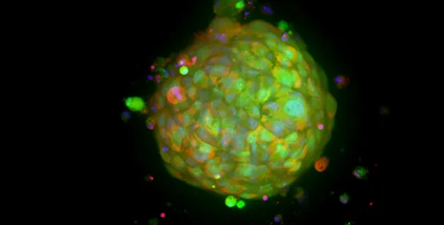

Intestinal organoids

Image Credit: Molecular Devices UK Ltd

They are derived from biopsies of histologically normal duodenal mucosa and reproduce healthy intestinal epithelium.

Intestinal organoids

Image Credit: Molecular Devices UK Ltd

3D tissue models called intestinal organoids replicate the features of the intestinal lumen and the surrounding intestinal epithelium.

Intestinal organoids are valuable for researching intestinal cell biology, regeneration, differentiation, and disease phenotypes, including the effects of certain mutations, the microbiome, or the inflammation process, because of the cell composition and organization of the epithelium.